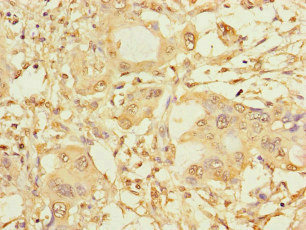

Immunohistochemistry of paraffin-embedded human pancreatic cancer using CSB-PA022470LA01HU at dilution of 1:100